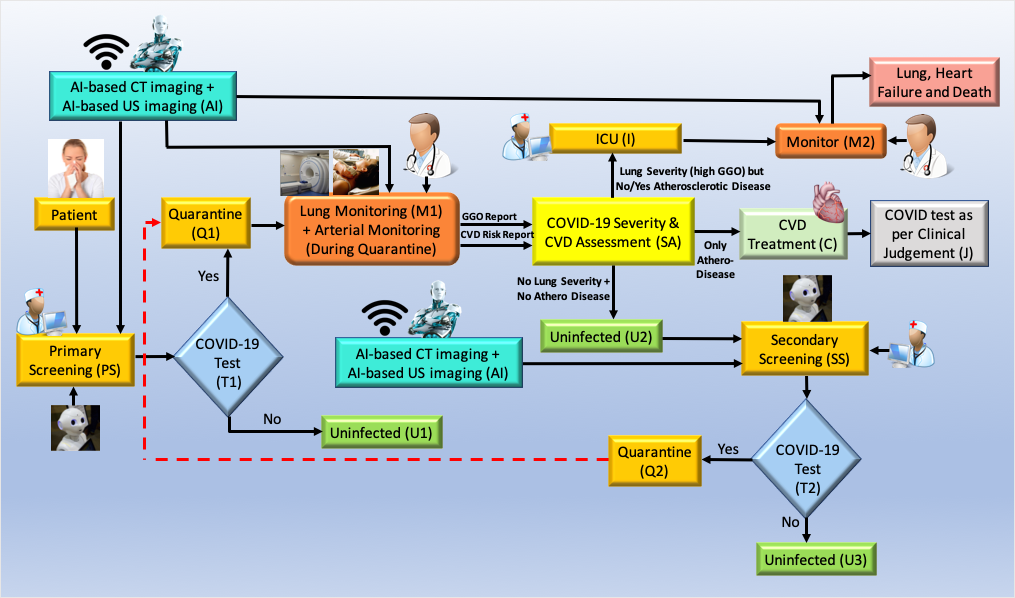

There are two major components for COVID19 screening: (i) primary and (ii) secondary. Fig. 12 shows the pictorial representation of the workflow during COVID-19 screening and diagnosis along with the role of AI for CVD screening.

Fig. 12.

Fig. 12.Role of AI-based CVD risk assessment during pandemic (Courtesy of AtheroPoint™, CA, USA).

Primary screening: The patient undergoes screening with the help of a robot and AI in the COVID-19 framework. Questions are asked considering basic symptoms and based on the answers received, the robot analyses and to move forward if there is a need for screening tests like the RT-PCR test (shown as T1, diamond box). Note that the cross-questioning is done when the patient first appears at the clinic or hospital doors. The analysis is done with the help of the AI-based machine intelligence system and telemedicine (TM) right at the outset (shown in the yellow ellipse, where the nurse and robot sign is depicted). Based on the results of the RT-PCR test at the T1 junction (shown in diamond box), the patient needs to be quarantined (Q1, marked yellow) if the test is positive, or the patient is uninfected by COVID-19, if the test is negative (marked green, U1).

Outcome of risk assessment box (SA):While the patient is in quarantine, risk assessment is performed using AI-based system during monitoring (shown using M1). During the monitoring process, the doctor interacts with the patient to understand (a) his lung condition and (b) atherosclerotic arterial condition. The lung condition is evaluated using X-rays/CT imaging embedded with AI. The atherosclerotic arterial condition is evaluated non-invasively using carotid ultrasound for CVD risk. The output of the monitoring function is fed to the risk assessment box (SA), to take appropriate decisions on three fronts: (i) worsening lung condition and need for ICU, or (ii) worsening of CVD condition and need for CVD treatment, and (iii) uninfected.

There are three outcomes from the risk assessment box (SA). (i) The patient’s Ground Glass Opacities (GGO) conditions if worsened (from the output of the monitor), however, no atherosclerotic lesions in the carotid arteries, the patient is categorized to be extremely symptomatic, evaluated further in Intensive Care Unit (ICU) under ventilation conditions. This situation is a dire necessity because the lung conditions have started to fill up with fluid (see Appendix Fig. 14). Note that, the patient is continuously monitored in the ICU (shown by monitoring function M2). (ii) If the lung conditions are not worse (very low GGO), while the carotid arteries show plaque burden, the patient undergoes CVD treatment (C). In the last outcome (iii) the patient neither has lung worsening nor arterial deterioration, therefore he is considered uninfected (U2). Note that, since the patient was quarantined (Q1) and the risk assessment (marked as A) was performed using AI based imaging followed by CVD treatment (marked as C), the patient is assessed by the doctor based on clinical judgement (marked as J). Finally, once the patient is uninfected (U2), the long COVID process triggers where the patient can be retested for COVID (secondary screening, marked SS). If found positive, the feedback loop triggers again for quarantine (Q1) or if negative, free from COVID-19 (U3, marked green).

The role of AI for CVD risk is evaluated using a machine learning system where the imaging data can be taken to predict the CVD risk at the vascular level [31, 140, 187]. The idea is to acquire the carotid scans of the patient, collect the plaque image-based phenotypes and predict the risk using a machine learning system. The AI component requires only the trained model shown by green colour labelled as Imaging-based AI with the AI logo of a robot on it. The output of the machine learning system is to tell the clinician monitoring the patient (M1) if the risk of CVD is low, moderate or high. Based on this colour-coded scheme, the patient undergoes CVD risk assessment (marked as SA). This can involve ground-glass opacity evaluation [241] of the CT lungs or if there is any pulmonary embolism [275]. Thus, the concept shows the role of AI-based CVD screening for diagnosis during pandemic times.